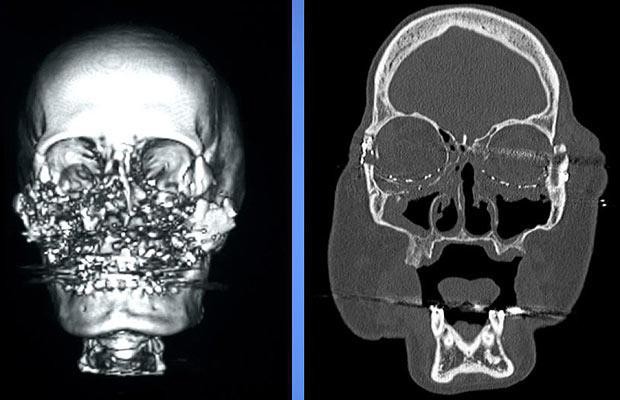

Phát súng oan nghiệt ấy không giết chết Connie nhưng đã thổi bay toàn bộ gương mặt của cô. Mắt, mũi, má, miệng… tất cả đường nét trên gương mặt người vợ đáng thương đã bị phá hủy chỉ còn lại hàng trăm mảnh đạn và xương vỡ lộn xộn. Sau khi bắn vợ, Tom dùng súng tự sát nhưng anh ta cũng may mắn thoát chết.

Gương mặt của Connie bị súng bắn vỡ vụn. Hình ảnh trước và sau khi phẫu thuật.

Tháng 12 năm 2008, một phép màu kỳ diệu đã xảy ra. Các bác sĩ đã tìm được một người hiến mặt thích hợp để làm cấy ghép cho Connie. Đây cũng là ca ghép mặt đầu tiên được thực hiện tại Mỹ. Sau cuộc phẫu thuật kéo dài 22 giờ liền, Connie đã được tái sinh với một khuôn mặt hoàn chỉnh. Tiến sĩ Maria Siemionow, Giám đốc nghiên cứu phẫu thuật thẩm mỹ tại Bệnh viện Cleveland, cho biết: “Gương mặt của bệnh nhân vẫn còn rất cứng, cô ấy bị mù mắt phải và bị ảnh hưởng thị lực bên mắt trái, tuy nhiên cô ấy sẽ có thể cười nói, ngửi và nếm thức ăn”.